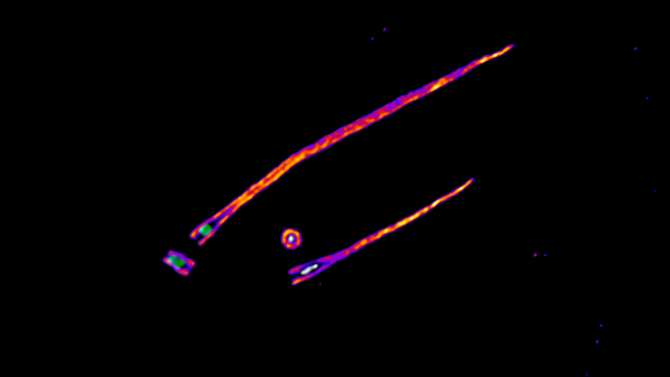

Imagen de microscopía de expansión de los centriolos con gammaTuRC (blanco) en el lumen y cilios asociados, extensiones con forma de cabello que funcionan como “antena” de la célula. (Imagen: IRB Barcelona. CC BY-NC-ND)

“Tuvimos que combinar ensayos funcionales con microscopía de expansión y microscopía superresolución para localizar gammaTuRC en los cultivos de células humanas dentro de los cilindros del centriolo y ver cómo actúa como estabilizador del centriolo, independientemente de su función en la generación de microtúbulos”, señala la Dra. Nina Schweizer, primera autora del trabajo y ex investigadora postdoctoral del IRB Barcelona.